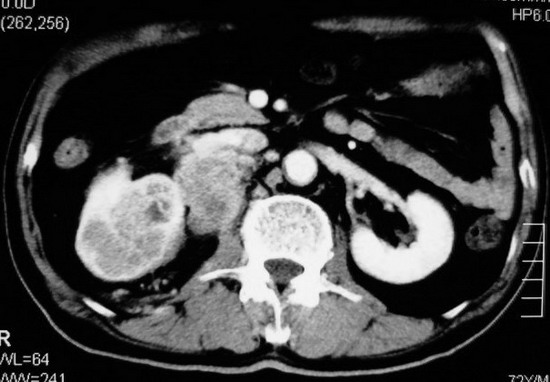

以下是引用杀毒软件在2008-11-17 19:15:00的发言:[br]考虑------右肾癌合并肾静脉---同侧肾上腺受侵可能性大

以下是引用zjzjr在2008-11-17 20:45:00的发言:[br]考虑------右肾癌合并肾静脉---同侧肾上腺受侵可能性大及腹膜后淋巴结转移.